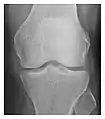

Figure 9: Proximal metaphyseal fatigue fracture of the tibia in a 27-year-old recent male military recruit. (a) Anteroposterior radiograph is within normal limits. (b) Coronal T1-weighted MR image shows a marked linear hypoattenuation along the medial tibial metaphysis (arrow) surrounded by diffuse hypointensity in keeping with posttraumatic edema.[1]